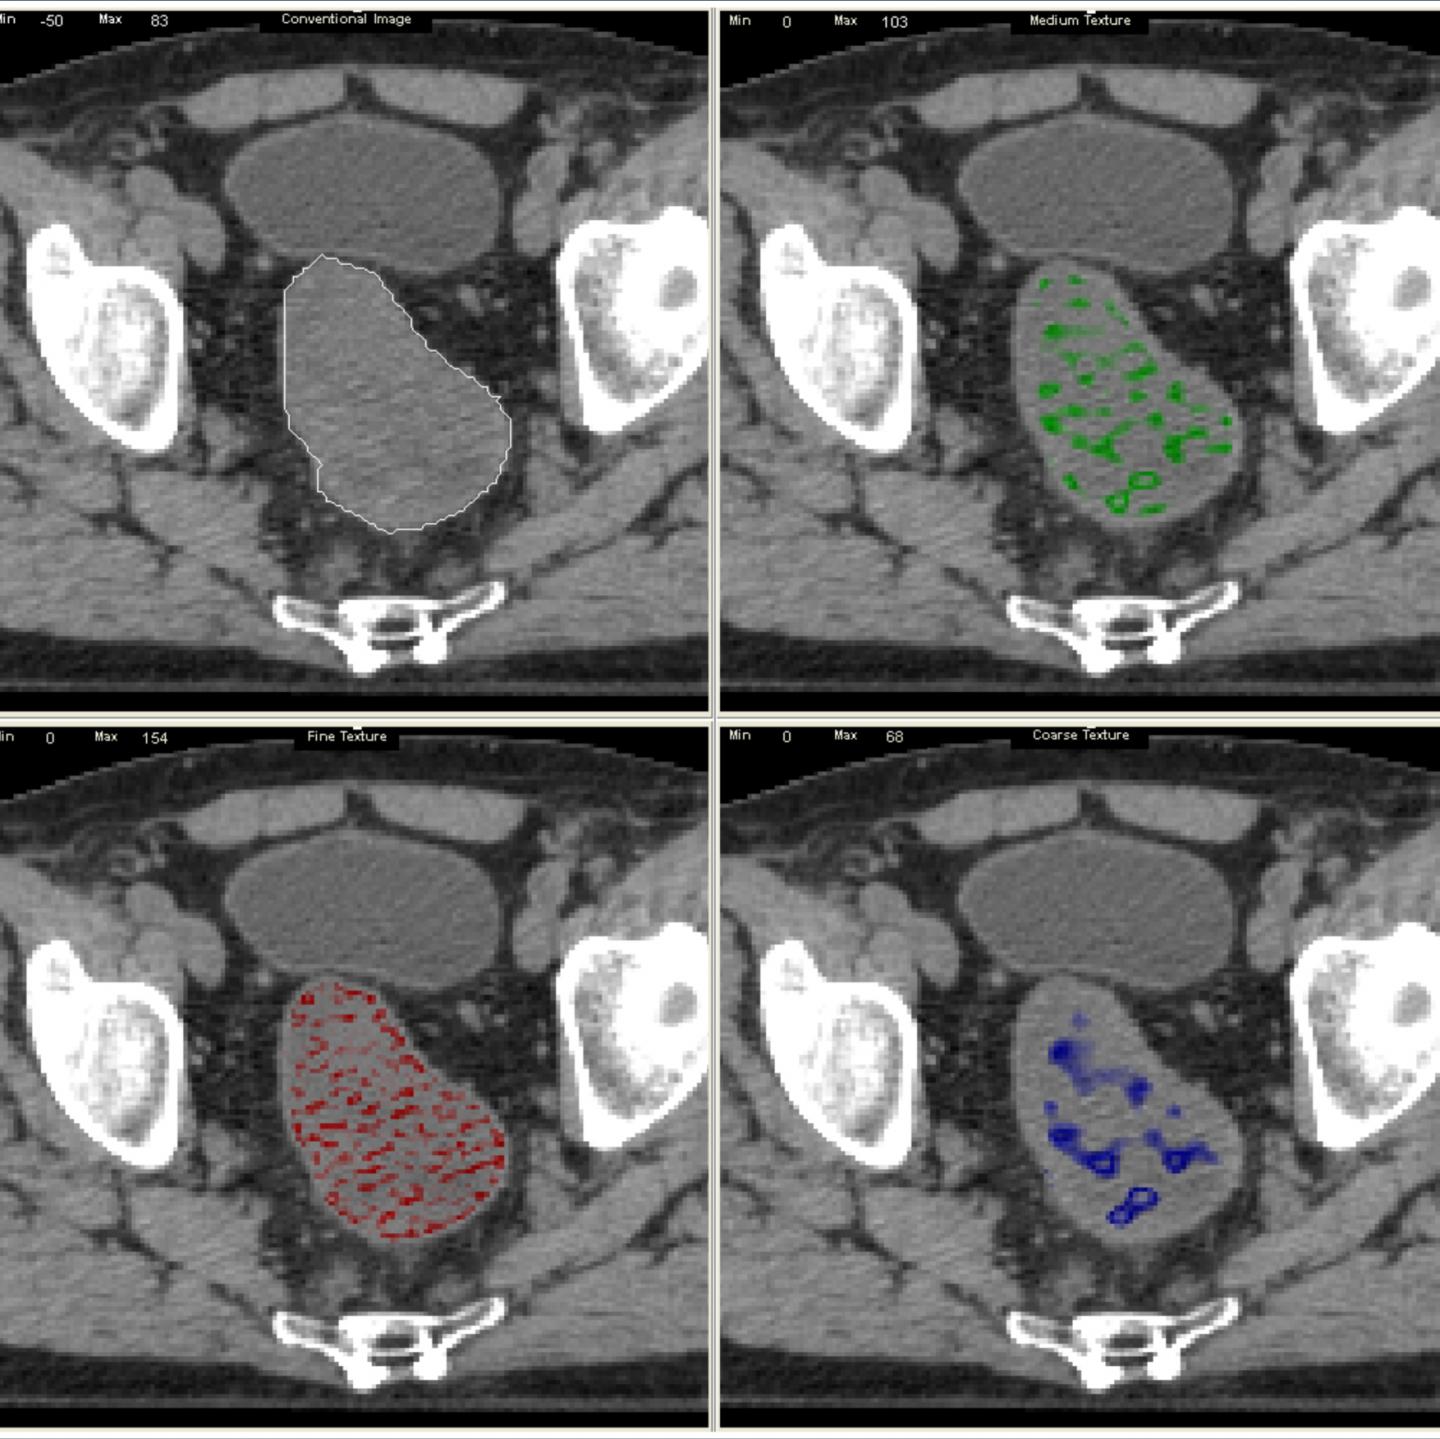

A novel medical-imaging technology, TexRAD, which analyses the texture of tumours, has been shown in trials to enable early diagnosis of those bowel-cancer patients not responding to the standard cancer therapy better than other available tumour markers.

Dr Balaji Ganeshan, one of the Sussex academics whose research led to the development of the technology, said: "By using TexRAD to scan for subtle anomalies in a tumour's texture, researchers have been able to spot more quickly when treatments are - or are not - working and adjust treatment accordingly.

"And because TexRAD simply provides an additional layer of software analysis of the MRI and CT scans that already exist as part of routine clinical practice, it is non-invasive from the patient's point of view and potentially cost-effective to the healthcare provider."

Based on the initial research by Sussex academics, TexRAD develops and markets a radical new imaging software that can extract vital additional information from routinely acquired whole-body diagnostic images of patients with cancer and other diseases and can assist clinicians in improved decision-making, i.e. prognosis, disease characterisation and response to treatment. It provides for the first time a commercially available imaging platform suite further developed under medical regulatory environment (for potential clinical use) dedicated for undertaking textural analysis of tumours.